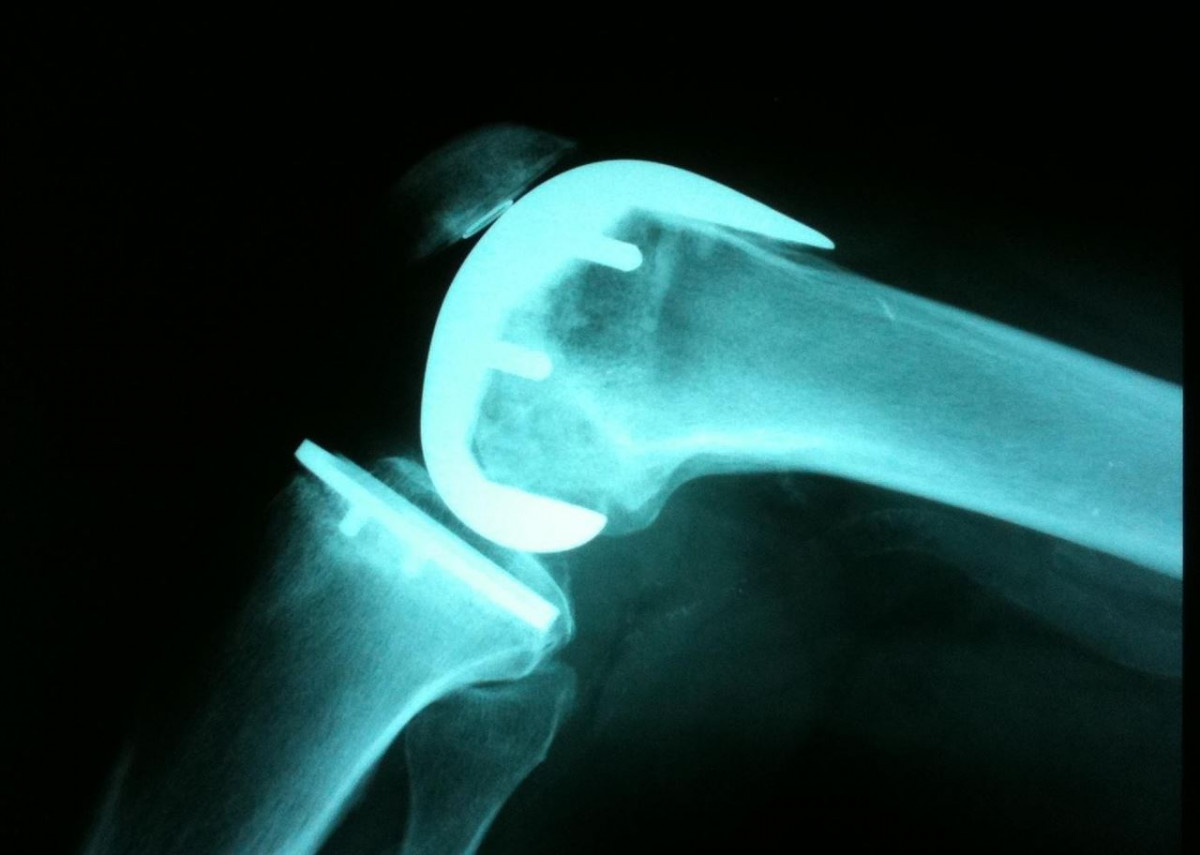

CatalunyaPress.- Un total de 47 cirujanos ortopédicos están imputados en este caso que investiga las presuntas irregularidades de las prótesis defectuosas de rodilla y cadera, principalmente de la empresa Traiber.

En total, 47 cirujanos ortopédicos están imputados en este caso del que se ha estado haciendo eco Catalunya Press y que investiga las presuntas irregularidades de las prótesis defectuosas de rodilla y cadera, principalmente de la empresa Traiber.